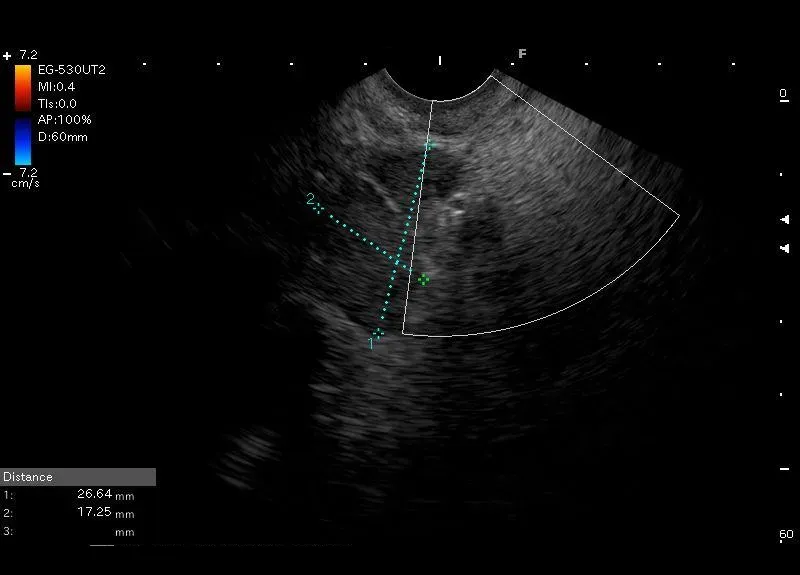

Powiększony węzeł chłonny